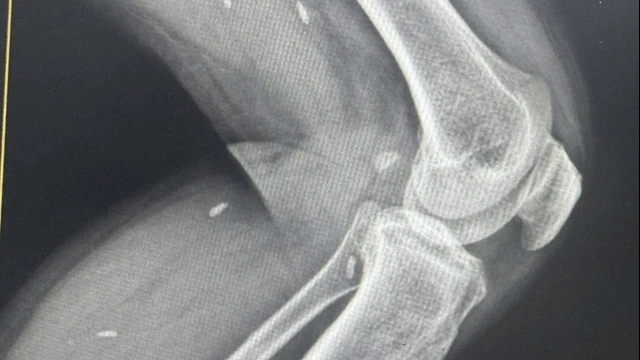

Theo Bệnh viện Đa khoa tỉnh Vĩnh Phúc, bệnh nhân N.X.N nhập viện cấp cứu ngày 24/9/2022 trong tình trạng: Tỉnh, đau ngực âm ỉ sau xương ức, kèm theo nôn ra thức ăn có lẫn dịch, da và niêm mạc hồng, người mệt mỏi. Bệnh nhận có tiền sử tăng huyết áp, bệnh nhân được bác sĩ chẩn đoán nhồi máu cơ tim cấp và được can thiệp mạch vành cấp cứu, đặt stent động mạch vành vị trí RCA I-II và được chuyển điều trị tại khoa Hồi sức tích cực – Chống độc. Tại đây, bệnh nhân đột ngột mất ý thức, điện tâm đồ cho hình ảnh rung thất, ngừng tuần hoàn. Các bác sĩ ngay sau đó đã khẩn trương tiến hành sốc điện ngoài lồng ngực, hồi sức tim phổi.